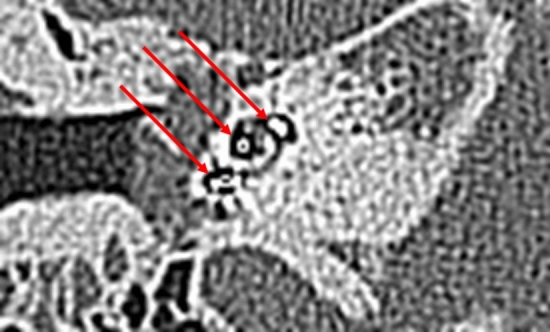

At the first turn, the estimation of the electrode position depends on the estimation of the basilar membrane and the diminishing localisation of the T2 signal by the electrode. In Fig. 5, diminishing occurred above the T2 signal and the basilar membrane signal, indicating fluid. This indicated the pattern of an electrode translocated into the scala vestibuli. Figure 7 of the same patient (No.10) confirms the irregular high position of the electrode in the first turn. In Figs. 3 and 4, the signal diminished above the electrode and the basilar membrane, indicating an electrode position in the scala tympani. Figure 6a and b are exemplary DVT of regular electrode positions at the floor of the basal and the first turn.

Figure 5.

Modiolar electrode, first turn, HFMS SV Position. Star represents diminishing electrode signal, arrow represents basilar membrane. Pat.No.10.